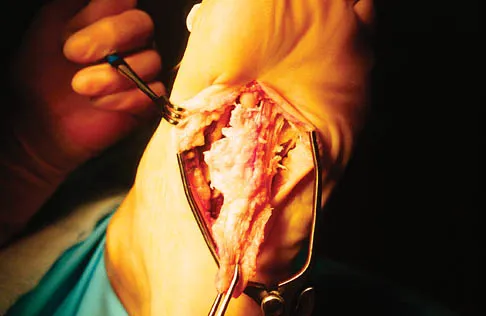

A 56-year-old woman has a painful mass on the bottom of her left foot, and orthotic management has failed to provide relief. Examination reveals that the mass is contiguous with the plantar fascia. An MRI scan shows a homogenous nodule within the plantar fascia. Resection of the tumor is shown in the clinical photograph in Figure 39. What type of cell is most likely responsible for the formation of this tumor?

Explanation